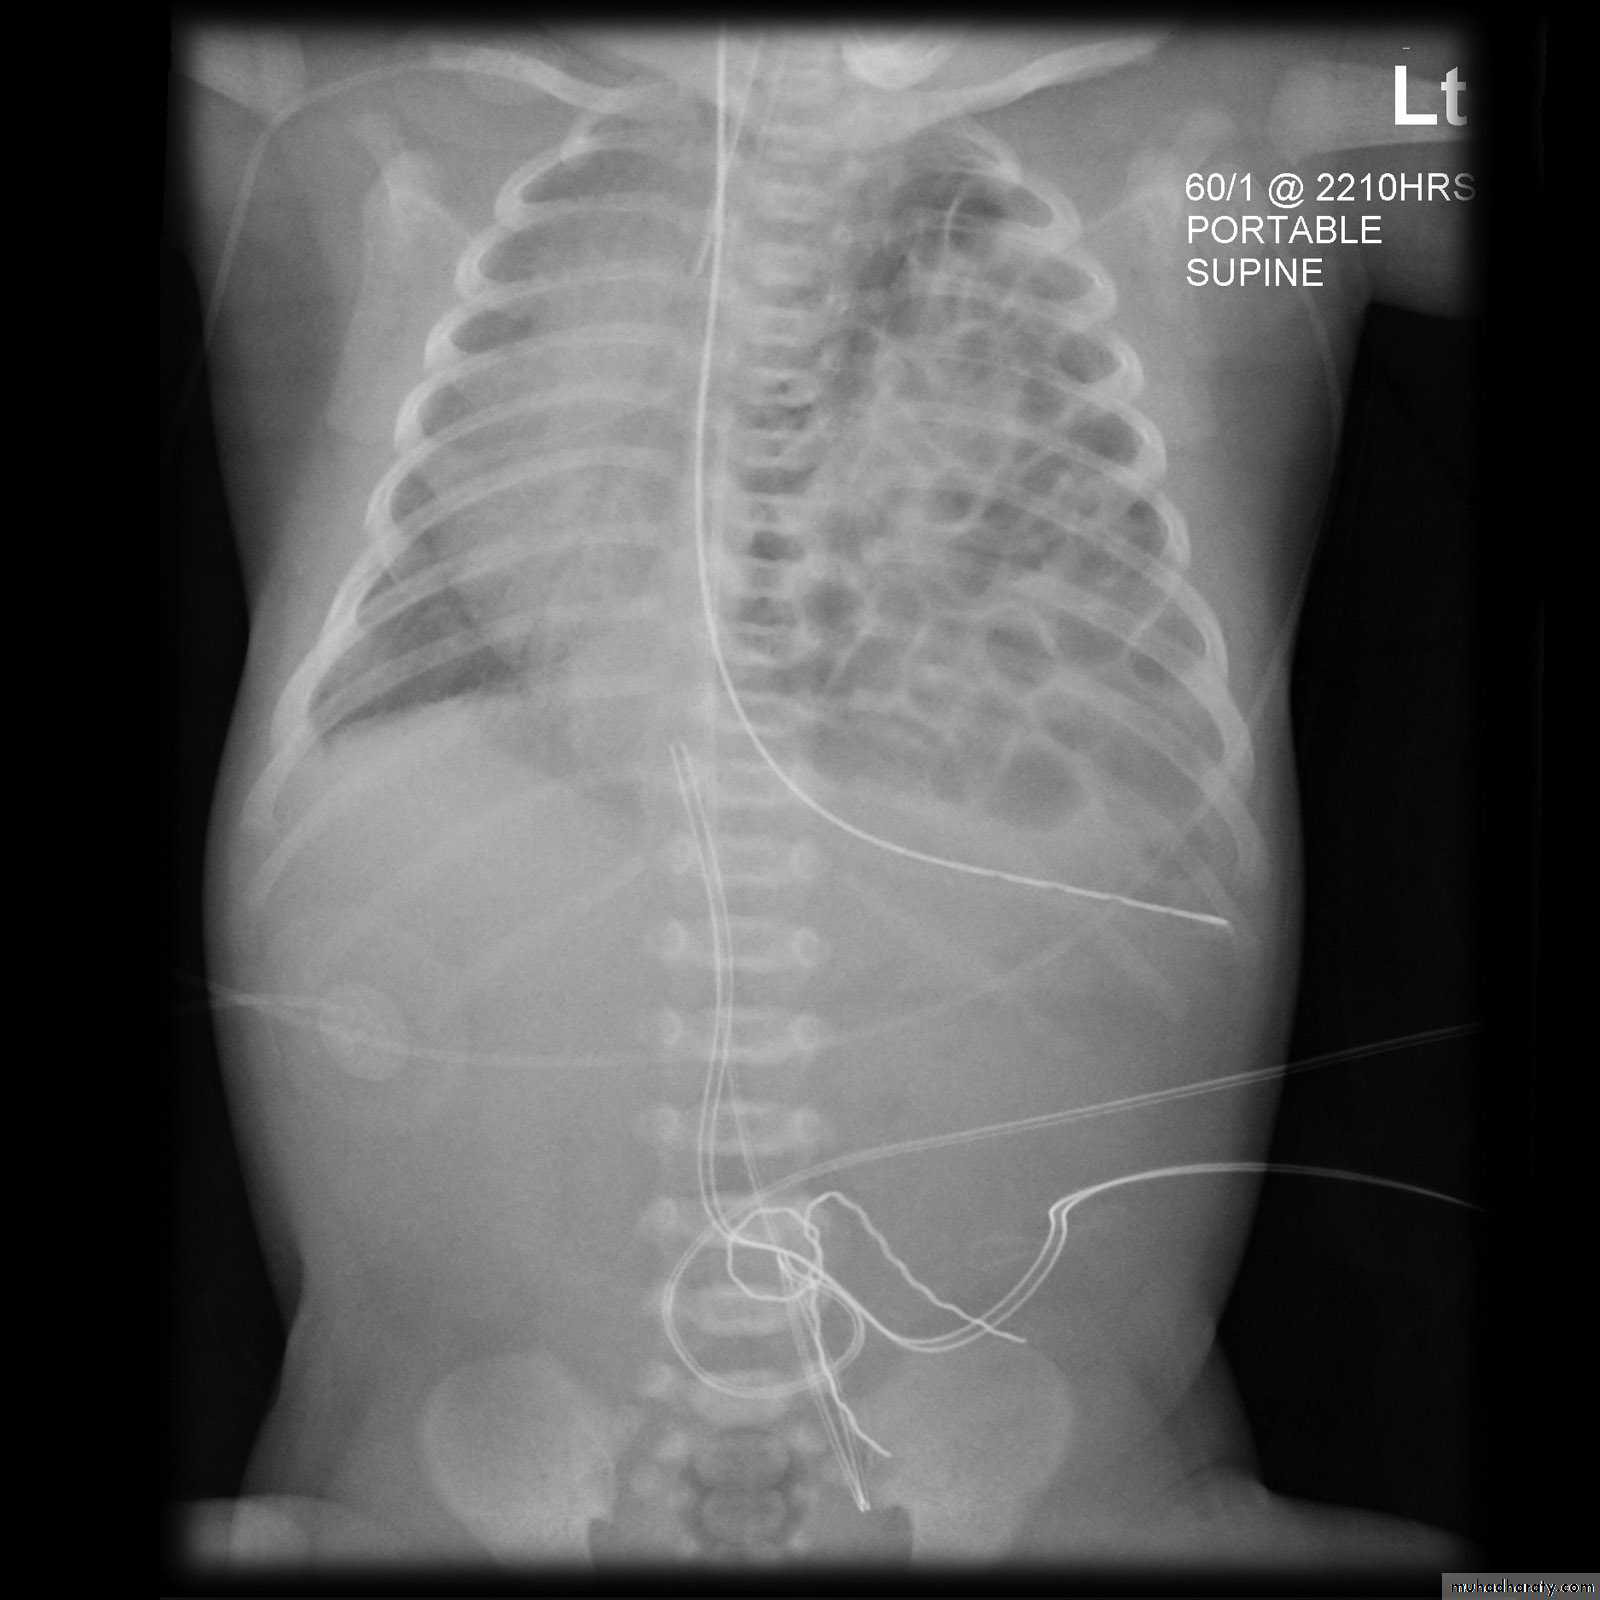

DDX of soap bubble appearance of the hemi thorax

79.Diaphragmatic hernia

congenital cystic adenomatous malformationSoap bubble appearance in the left hemithorax with shifting of mediastinum to the right

Left hemidiaphram cannot be seen

Presence of nasogasric tube

Soap bubble appearance in the left hemithorax with air fluid level

Shifting of mediastinum to opposite side